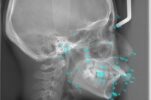

レントゲンでは肉眼では確認できない、歯の根っこの状態や親知らずの有無を確認します。また、歯全体(パノラマ)だけでなく、セファロ(セファログラム)と呼ばれる頭部のレントゲンも撮影します。頭部の撮影をすることで、その方の骨格や歯の傾き、口元のバランスなどを把握します。

[セファロ]